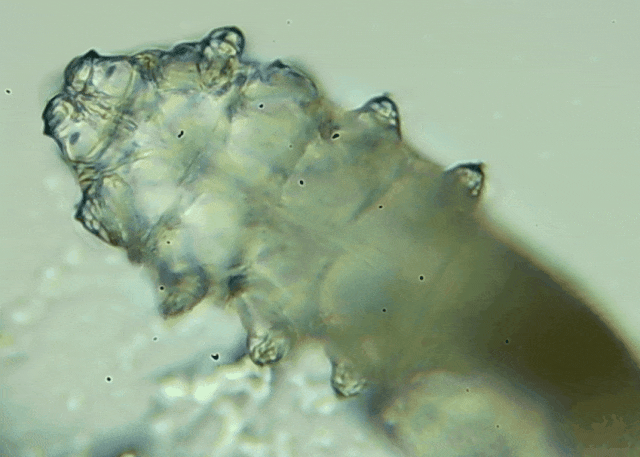

蠕形螨是一類肉眼看不見的寄生螨,常見的有毛囊蠕形螨和皮脂蠕形螨,常駐在人類的毛囊和皮脂腺里,尤其是眼睛的瞼板腺和睫毛根部。數(shù)量少時,蠕形螨能與人體“和平共處”,但一旦你免疫力下降、油脂分泌旺盛或清潔不到位,他們就會以你難以想象的速度瘋狂繁殖。